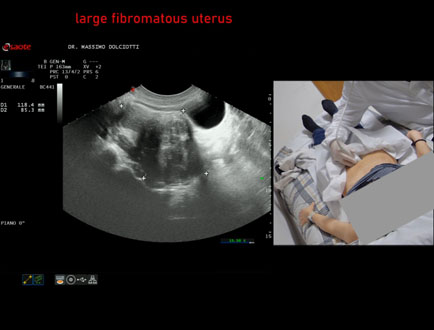

Data inserimento: 29/04/2026

Ecografia del: 16/04/2026

Strumento: Esaote MyLab Eight

Sonda: Convex Multifrequenza 1-8 MHz

Età Paziente: F 58 anni

Motivazione dell'esame: follow up di fibromi all'utero

Commento all'esame: le immagini ed il video documentano l'utero aumentato di volume, con diametro longitudinale di 118 x 85 mm, ad ecostruttura spiccatamente disomogeneo per la presenza di multipli fibromi. Il rene destro presenta ecostruttura e morfovolumetria normale, con diametro bipolare di 109 mm (v.n. 90-120 mm) x 55 mm e parenchima renale dello spessore di 15 mm (v.n. > 13 mm), con idronefrosi di 2° grado.

Conclusioni: grande utero fibromatoso ed idronefrosi di 2° grado al rene destro (large fibromatous uterus and 2° degree hydronephrosis of the right kidney).

In collaborazione: Dr.ssa Marica Manfredi - Ancona, Dr. Ilir Qose - Ancona

Presentazione: Dr. Massimo Dolciotti - Ancona

Elaborazione digitale: Andrea Dini - Ancona